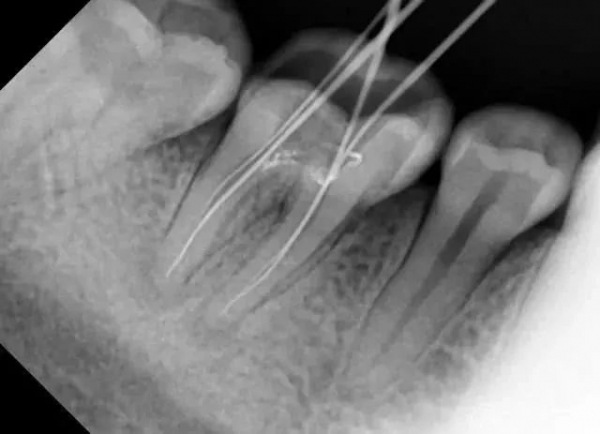

患者是30多歲的年輕男子,紅色標(biāo)記那顆牙松動(dòng),要求拔牙,開始嫌麻煩不愿拍片,后來經(jīng)過再三勸說還是拍了片。結(jié)果把所有人包括他自己都嚇了一跳。估計(jì)是良性,具體還得去醫(yī)院住院手術(shù)做病理檢查,所以大家不要忽視一張片子帶來輔助檢查的重要性。

試想,如果沒有拍片,直接貿(mào)然拔牙,一旦出現(xiàn)問題......一張牙片,“救”了診所,也救了患者!牙齒的硬度比骨骼還高,僅靠肉眼檢查是無法得知牙齒內(nèi)部情況的。

因此,如果牙齒出了問題,齒科醫(yī)生就需要有“透視”功能的X線片來檢查。通過x線片不僅能了解牙齒本身的病變情況,還可以了解牙根下有沒有囊腫、周圍骨頭有沒有吸收以及牙槽骨內(nèi)是否有埋伏牙、多生牙等。依據(jù)X線片綜合分析,可以提高齒科醫(yī)生診斷治療牙齒的準(zhǔn)確性和成功率。常見的牙科放射檢查包括曲面體層片( 全景片 )、小牙片、頭顱正側(cè)位片、全頭顱 CT、錐形束 CT( CBCT )等。由于牙齒下部隱藏在牙槽骨中,口腔醫(yī)生要了解牙齒的整體情況就需要拍攝全景片;要了解個(gè)別牙根及周圍變化,則選擇拍攝小牙片。醫(yī)生要判斷牙槽骨是否符合種植條件,或者了解埋伏阻生齒的三維位置以及其他頜骨內(nèi)病變組織的形態(tài)大小時(shí),則需要進(jìn)一步拍攝 CBCT 。所以,拍牙片是一種幫助齒科醫(yī)生進(jìn)行診斷、治療、療效評(píng)估的重要手段,治療前用于發(fā)現(xiàn)病變程度、范圍;治療中用于引導(dǎo)治療、確定治療范圍和深度;治療后用于觀察療效。輻射分為電離輻射(如X光)和非電離輻射(如手機(jī)、微波爐),這里主要講述的是電離輻射。電離輻射的測(cè)量單位是西弗(Sv),但西弗是個(gè)非常大的單位,因此通常使用毫西弗(mSv)和微西弗(μSv),1Sv=1000mSv,1mSv=1000μSv)根據(jù)國(guó)際放射防護(hù)委員會(huì)(IRPA)提供的信息,每人每年受到的輻射劑量大約在2.5毫西弗左右,這個(gè)數(shù)值受地域緯度的影響而波動(dòng)。其中大約80%來源于自然界,20%來源于人工輻射。而拍牙片是什么樣的輻射水平呢?根尖片為 5.2 μSv ,全口根尖片為 72.32 μSv ,曲面體層片為 10 ~ 23 μSv ,頭顱正位片為 1 ~ 5 μSv ,頭顱側(cè)位片為 1 ~ 3 μSv ,讓人「聞風(fēng)喪膽」的 CBCT 劑量一般也在 300 μSV 之內(nèi)。為了幫助大家更容易理解,我們用單位面積內(nèi)的香蕉數(shù)量表達(dá)輻射強(qiáng)度。之所以選擇香蕉,是因?yàn)橄憬陡缓浽?,天然鉀?dāng)中約有0.0117%的放射性鉀——鉀40,而鉀40的半衰期長(zhǎng)達(dá)12億5千萬年(地球歲數(shù)大約45億年)。